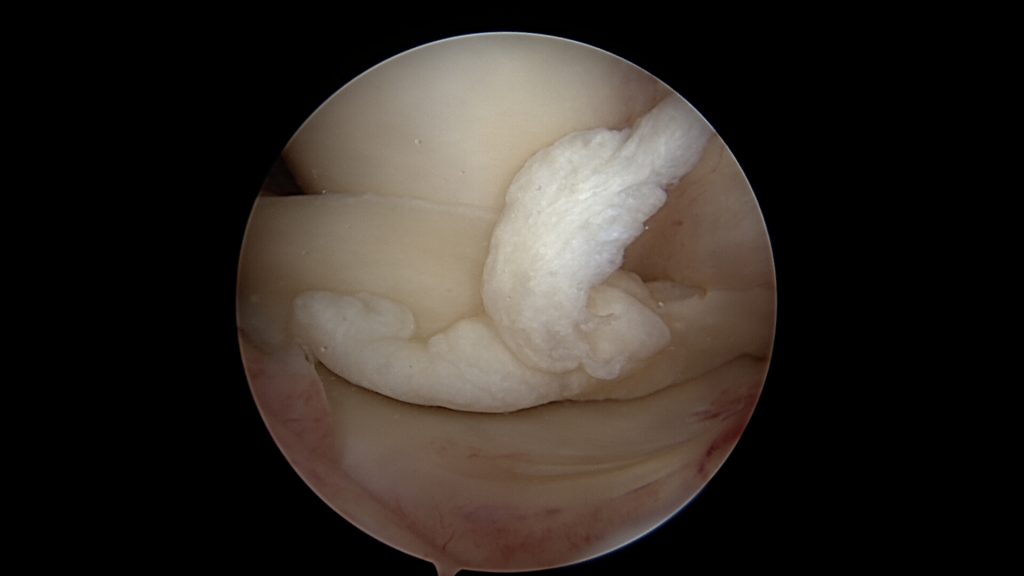

W przypadku dużego urazu, gdy oderwaniu ulegnie duży, tylny fragment łąkotki (uszkodzenie typu „rączka od wiaderka”) rokowanie wbrew pozorom jest dobre. Linia oderwania się łąkotki przebiega w jej tak zwanej „części czerwonej”, dobrze ukrwionej.

Co prawda uszkodzona tylna część łąkotki znajduje się teraz w przedniej części stawu, ale w większości przypadków jest jednym kawałku. Dominującymi objawami po urazie jest ograniczenie wyprostu kolana oraz dosyć szybko występujący obrzęk kolana z powodu powstającego krwiaka. Jeśli nie będziemy się starali wyprostować kolana na siłę oraz w miarę szybko wykonamy zabieg operacyjny to nie ulegnie ona dalszemu uszkodzeniu.

Potwierdzenie rozpoznania tego uszkodzenia następuje podczas zabiegu bardzo szybko. Zaraz po wprowadzeniu optyki do stawu po prostu widzimy łąkotkę nie tam gdzie powinna być, czyli tuż przed kamerą. Po wykonaniu inspekcji wszystkich dostępnych części stawu dokonuje się odświeżenia miejsca uszkodzenia oraz „repozycji” uszkodzonego fragmentu łąkotki (przepchnięcia jej na swoje miejsce). Następnie przy pomocy szwów zakładanych artroskopowo mocują się ją na swoim miejscu.